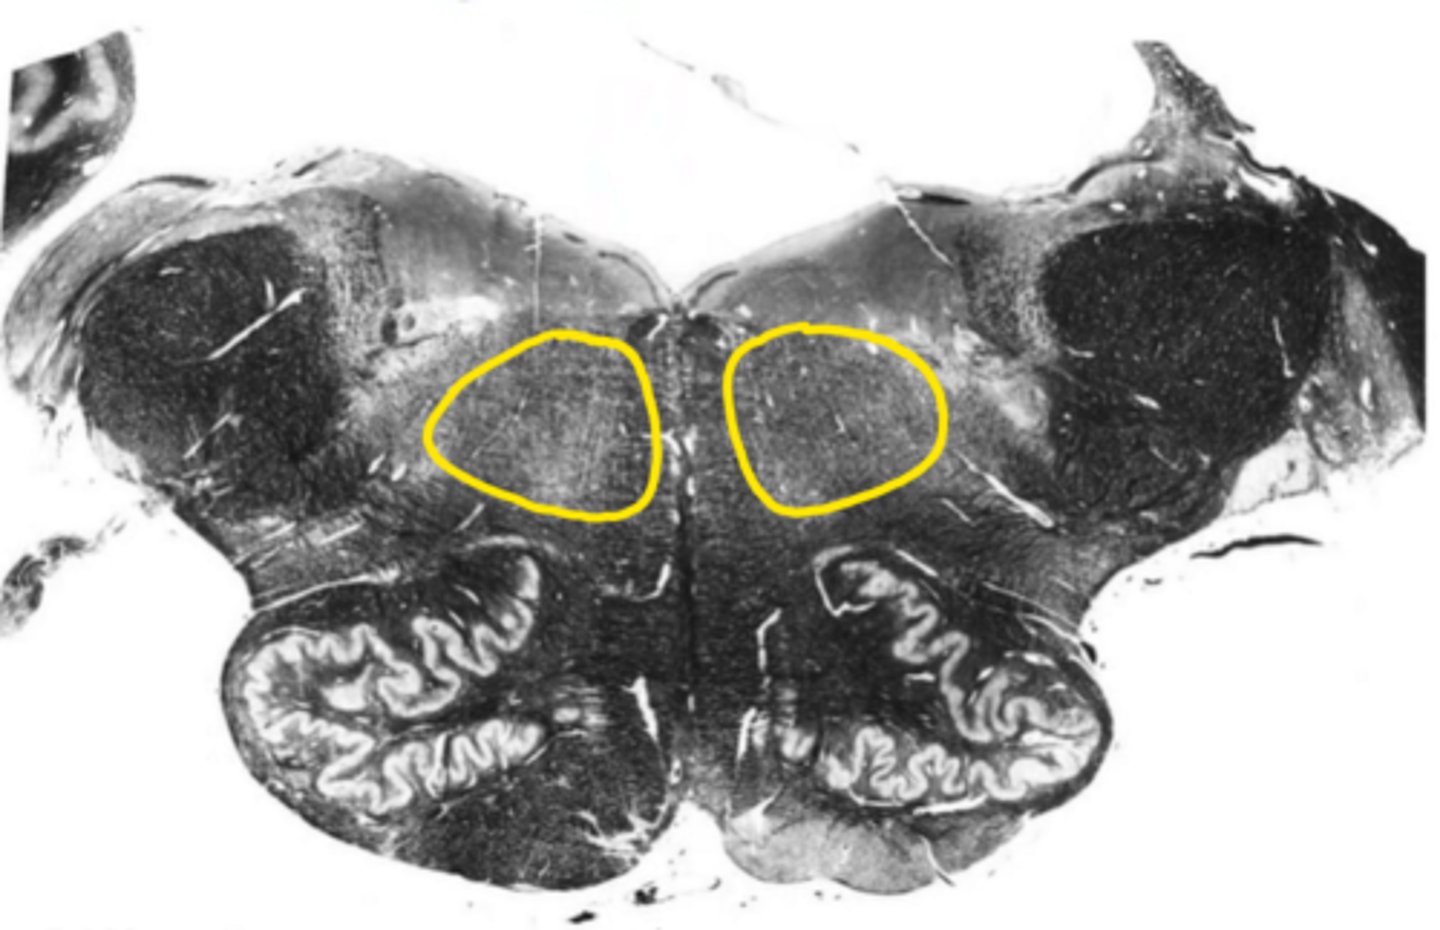

central canal

ID the space

central gray

ID the structure

hypoglossal nucleus

ID the nucleus

gracile nucleus

cuneate nucleus

inferior cerebellar peduncles

reticular formation

internal arcuate fibers

ID the fibers

principle olivary nucleus

medial lemniscus

corticospinal fibers

anterior median sulcus

posterior median sulcus

closed medulla

ID the brainstem level